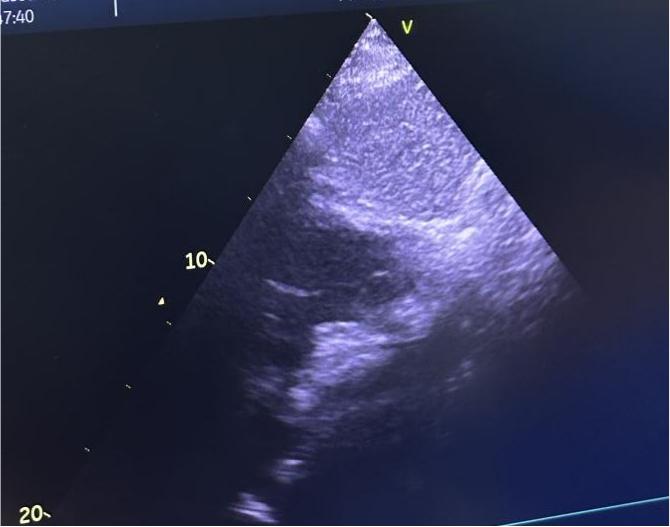

手术在局部麻醉下进行,通过股静脉穿刺建立介入通道,在超声及X线引导下,将可降解封堵器精准输送至房间隔缺损处。封堵器展开后完全覆盖缺损部位,即刻超声显示分流消失,三尖瓣反流显著减少,手术全程耗时约1小时。术后患儿生命体征平稳,无不适症状,次日即可下床活动。其家属对治疗效果表示高度认可:“孩子终于能像其他同龄人一样正常上学,上体育课了,感谢宋主任团队!”

术后超声